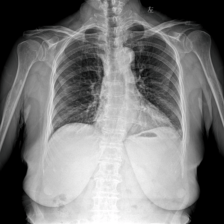

To pre-train a high-performance X-ray foundation model, the first thing we need to do is the collection of large-scale X-ray images. Therefore, a large-scale and high-resolution dataset that contains X-ray medical images is collected for the pre-training. Some representative samples are visualized in Fig. 3.